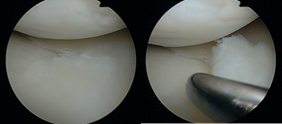

关节镜下半月板损伤的图片

关节镜下半月板修整缝合术